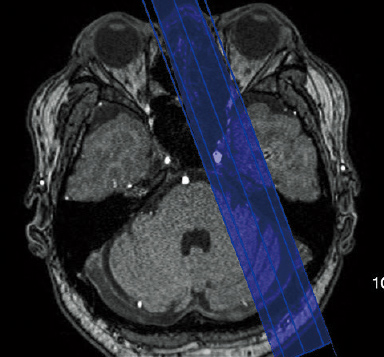

AutoPose*1

Skanogram işlevi, bilgilerin operatörler için bölgelerin kesit alanlarında hızlı bir şekilde görüntülenmesini sağlar.